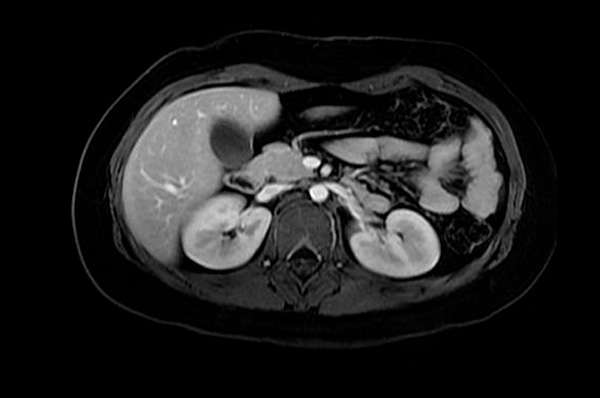

Gracias a las avanzadas técnicas, podemos estudiar los órganos abdominales (hígado, páncreas, etc) así como pélvicos (útero, ovario, próstata) con una gran diferenciación hística, que con el apoyo de medios de realce tisular (contraste) nos permiten un afinamiento en el diagnóstico. Es posible que estos estudios necesiten de la inyección de contraste, con lo que es recomendable que el paciente venga en ayunas. Puede que en algún momento de la prueba se le pida que realice apneas, todas ellas controladas y adaptadas a la capacidad del paciente

Ejemplos